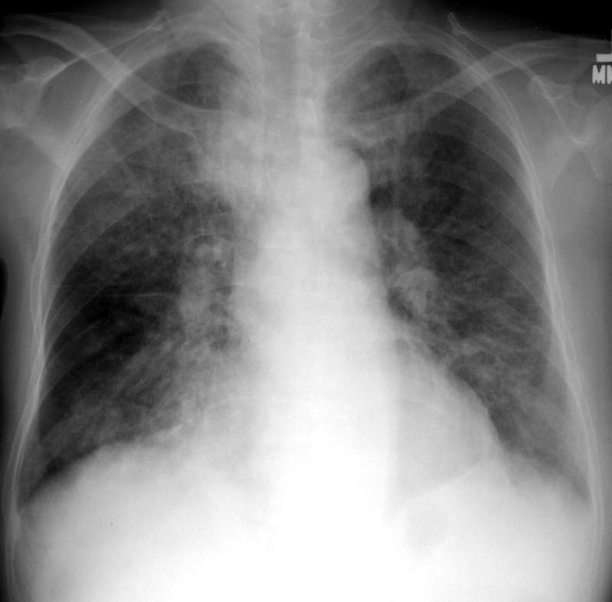

Which air space pathology is usually diffuse, seen as thin white lines and sometimes may present with a honeycomb appearance?

interstitial infiltrates

Are interstitial infiltrates specific or non-specific?

non-specific

NOTE: can be caused by many processes such as CHF, pulmonary fibrosis, collagen vascular diseases etc.